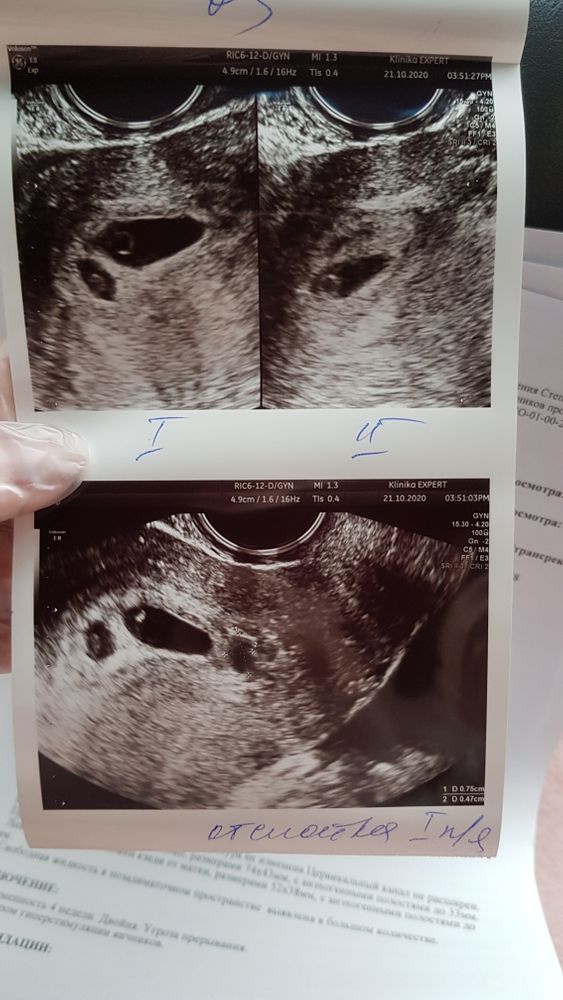

Я БЕРЕМЕННА !Девочки, 21.10 сделала узи на 25 дпп и сразу легла на сохранение (отслойка) но крови вообще нет.

Второй эмбриончик еле тянет. Сегодня сделали узи повторно, с первым все хорошо, отслойка меньше стала, а вот у второго сердце не услышали😞 но хоть эмбрион увидели. Как вы думаете может по сроку догнать? По акушерским 6,5 недель, по переносу 4 недели. Узист сказала догонит, врач говорит на вряд ли...